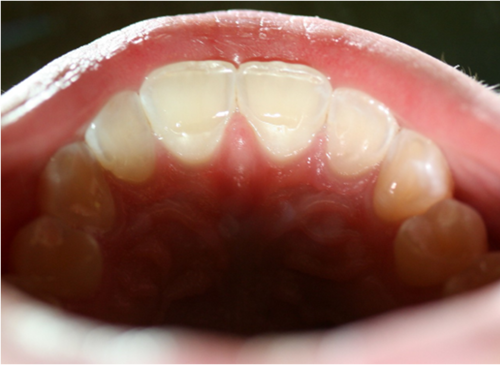

Eksempel på syreskader

Her ses forskellige eksempler på, hvor syre har ætset det meste af emaljen væk. Undersøgelser viser, at hvert 6. barn har syreskader.